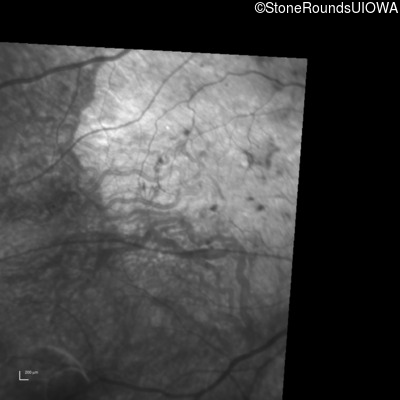

Infrared Fundus Photograph - Right - 20/100 +1

Exemplar

Infrared Fundus Photograph - Left - 20/200